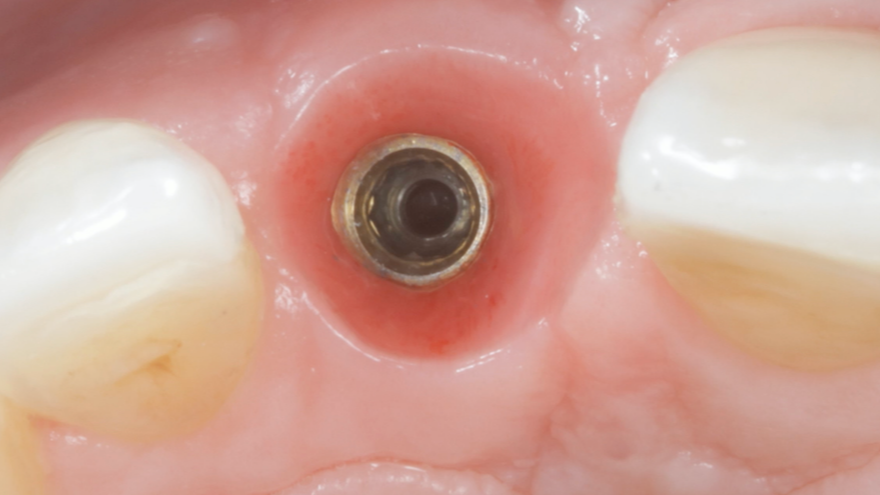

Removing a Broken Abutment Screw

Dr Sascha Jovanovic

What to do when your patient arrives in your office with panic in their eyes and the implant crown in their hands?Repairing a broken dental implant abutment screw requires careful handling and attention to detail. Here are t...